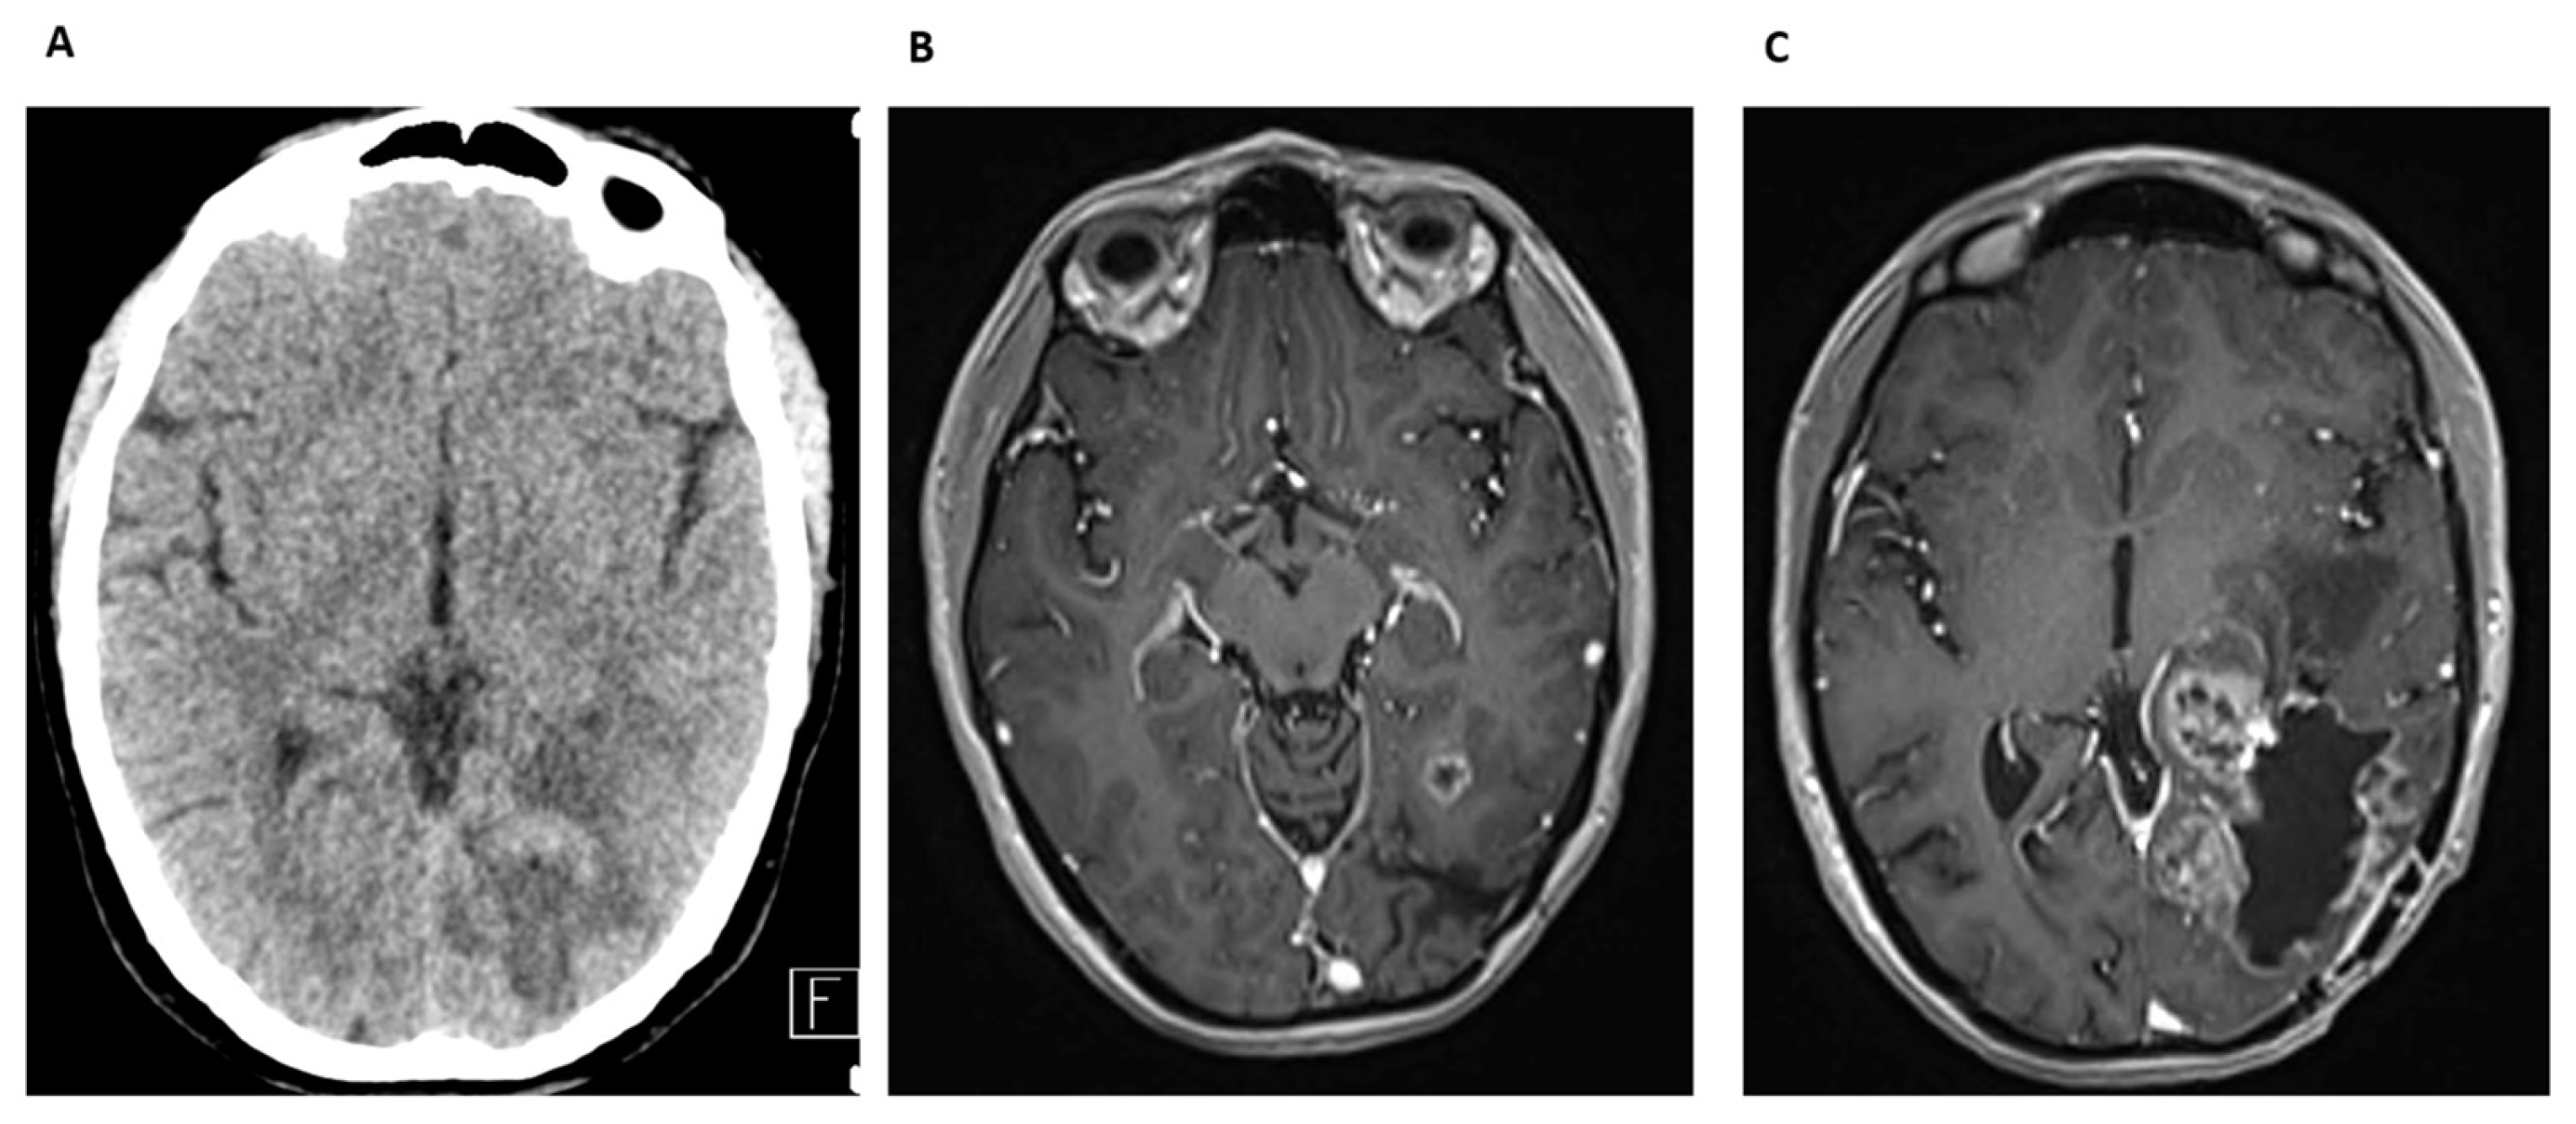

Case Report 1

Case Report 2

Case Report 3